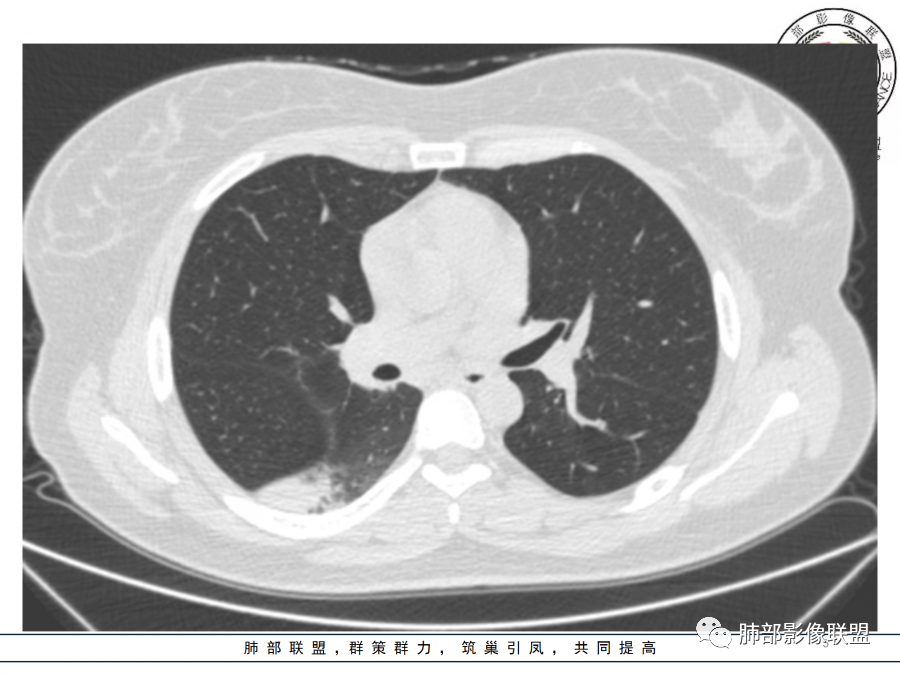

右肺胸膜下实变,病变跨多个叶生长,宽基底与胸膜相连,近端支气管穿行病灶内,并可见片状磨玻璃影,边界清,部分远端小支气管堵塞,支气管略有扩张,周围散发小结节,临床年轻女性,炎性指标高,发热六日,首先考虑感染性病变(肺链,奴卡,隐球,OP)鉴别淋巴瘤。

年轻女性,无明显诱因发热,体温略高,起病较急,有畏寒,右下肺紧贴胸膜下片状实变影,部分融合,外围有结节影,性质比较单一,类似于蘑菇兄弟,病灶周围伴有晕,支气管进入近端扩张远端堵塞,常规考虑感染,肺炎链球菌、隐球菌。

青年女性,发热咳嗽5天,炎症标志物升高。右肺下叶大片实变伴周围GGO,GGO内未见细网格,主体与胸膜平行,似多个病灶融合,实变区内见支气管部分进入,部分支气管受压狭窄,周围可见多发卫星病灶。支持炎性,考虑隐球感染,鉴别op。

年轻女性,急性起病,咳嗽,发热,黄痰,白细胞高,CRP基本正常,基础体健。CT提示右肺下叶实变,宽基底与胸膜相连,长轴平行于胸膜,可见支气管充气征,于病变中央截断,走形自然,胸膜下脂肪间隙可见,倾向于隐球菌,鉴别肺链,军团菌等。

年轻患者,右肺下叶大片状实变影,长轴与胸膜平行,内见含气支气管征,周围磨玻璃晕影。考虑感染性病变,隐球?

病灶长轴与胸膜平行,边缘有晕,病灶融合趋势,支气管进入,走行自如,考虑隐球菌肺炎。

年轻女性,急性发病,咳嗽咳痰五天,炎性指标升高,右肺下叶胸膜下大片实变影,周围见磨玻璃影,边界清晰,长轴与胸膜平行,呈融合趋势,支气管进入走行自然,远端截断,考虑炎性,隐球菌可能。

年轻女性,发热,急性发病,白细胞高,右肺下叶大片实变,长轴与胸膜平行,内见支气管走行,远端截断,周围有晕,晕边界清,考虑感染,隐球可能,鉴别淋巴瘤。

年轻女性,右肺下叶胸膜下多发实变、结节影,宽基底与胸膜相连,边缘模糊不清,实变内见支气管穿行,血象高,考虑感染性病变,大叶性肺炎?隐球?

青年女性,发热咳嗽急性起病,右肺下叶大片状实变密度影,长轴平行于胸膜,边缘模糊可见磨玻璃影及高密度结节影,实变内可见支气管穿行,直达病灶远端,考虑感染性病变,隐球菌可能大。

右肺胸膜下实变,病变跨多个叶生长,相互融合,宽基底与胸膜相连,支气管气象,并可见片状磨玻璃影,边界清,炎性指标高,发热六日,考虑感染病变,链球菌?腺病毒待排。

右肺下叶大片状实变影,长轴平行于胸膜,边缘模糊可见磨玻璃影,支气管进入,部分近端阻塞,考虑感染性病变,隐球菌,鉴别大叶性肺炎。

年轻女性,起病急,白细胞,C反高,存在感染。右下肺大片实变影,支气管充气征,长轴平行胸膜,似多个病灶融合,周围GGO,部分清,部分不清。考虑感染,隐球可能。

青年人,右肺多发团片状阴影,边缘模糊,周围可见磨玻璃影,内部有支气管空气征,考虑感染性病变,隐球菌感染可能。

右肺下叶大片状实变影,从外向内,长轴平行于胸膜,边缘模糊,可见磨玻璃影,支气管进入,远端部分阻塞,考虑感染性病变,隐球菌,鉴别淋巴瘤。

26岁,女性,发热、咳嗽5天。咳少量黄痰,起病急,病程短,白细胞及中性高,血沉及D-二聚体增高。胸部CT:右肺下叶大片实变,长轴沿胸膜分布,宽基底与胸膜接触,边界不清,周围GGO,部分团片影融合,病灶内可见支气管充气征,部分支气管进入病灶后阻塞。考虑:感染性病变,隐球菌?脓毒肺栓塞?鉴别:肺炎型肺Ca。

年轻女性,右肺下叶一大片实变影,似有多个结节影融合,周围有晕,内见支气管充气征,部分支气管进入后截断,病变近胸膜,长轴胸膜平行,考虑炎性,隐球菌首先考虑。

青年女性,影像表现右肺下叶胸膜下大片状实变影,近端见充气支气管征,边缘见片状磨玻璃影,下叶背段尚可见一结节。考虑感染性病变,隐球菌感染可能。

右下肺大片实变影,空气支气管征,边缘GGO,小叶间隔增厚,周围有蘑菇兄弟,基底宽,与胸膜平行,考虑隐球菌感染,鉴别肺炎型肺癌。

晨读:年轻女性,右肺胸膜下实变影,平行于胸膜,边缘磨玻璃影,内见支气管充气征,走形自然,略扩张。考虑感染性改变,隐球,肺链。2月发病,病毒性肺炎要考虑。鉴别淋巴瘤。

晨读:年轻女性,发热咳嗽5天。白细胞计数升高。右肺下叶大片状高密度影,边缘模糊,有实变 GGO,其内见支气管气相、无受压变细,无枯枝表现,其近端支气管无异常,右肺下叶背段见结节状影,定性考虑:炎症,隐球菌感染可能,炎症型肺癌不支持。

右下肺胸膜下大片状高密度影,其长轴与胸膜平行,病灶近端GGO模糊,部分支气管进入后阻断,支持感染性病变,考虑隐球菌